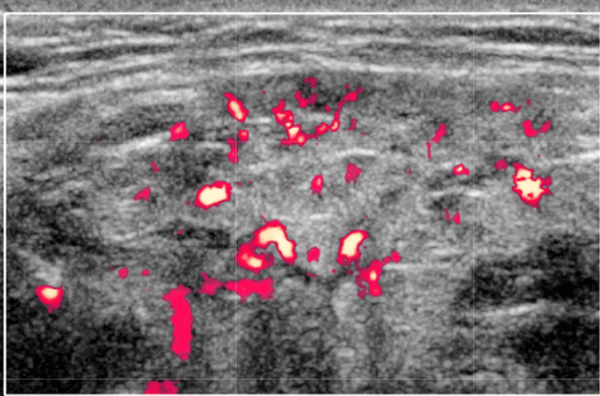

- Повышенная паренхиматозная васкуляризация при СШ на ультразвуковом сканировании с ЦДК

Цветной допплер. Повышенная паренхиматозная васкуляризация при синдроме Шегрена и коррелирует с тяжестью заболевания